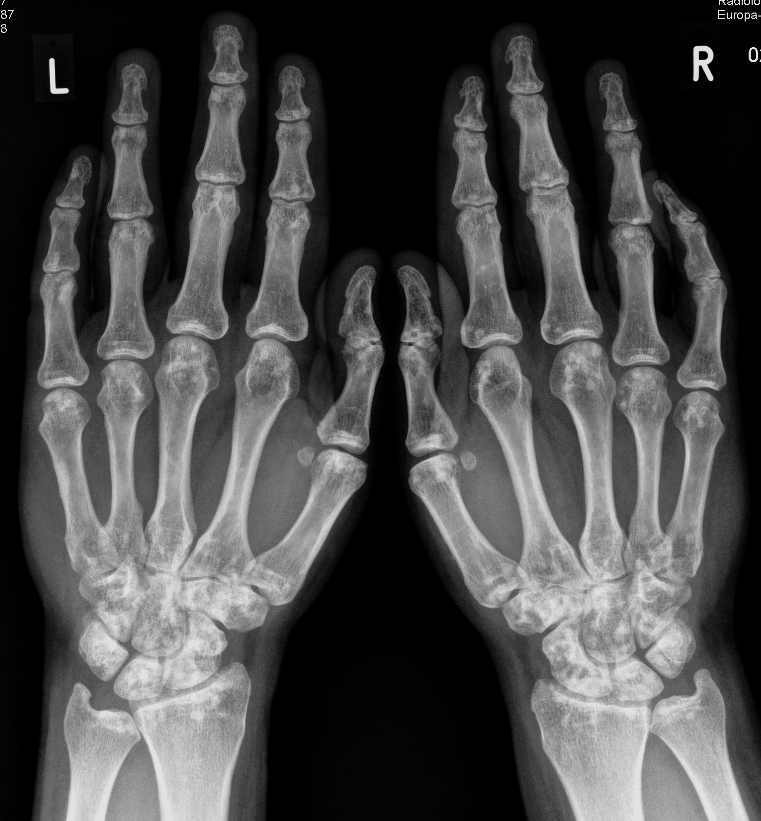

Beschreiben Sie die Befunde auf dem vorliegenden Röntgenbild der Hände und geben Sie die wahrscheinlichste Diagnose an.